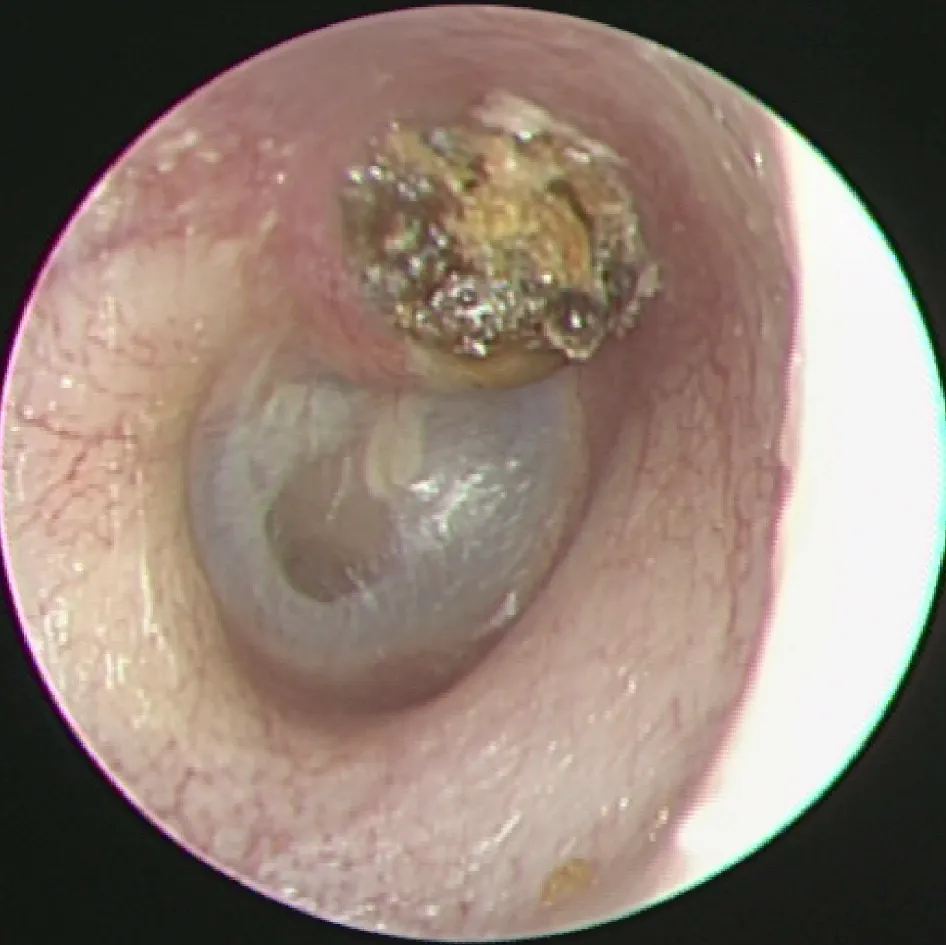

【109-1 醫學(六) 第20題】病人耳鏡檢查所見如下圖,最可能之診斷為: